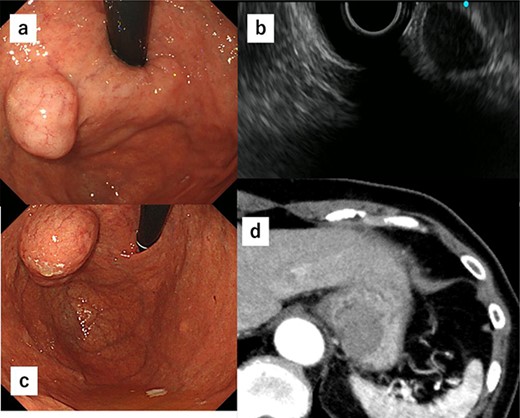

A 52-year-old man was diagnosed with acute cholecystitis after presenting to the emergency department of our hospital with right upper quadrant abdominal pain. Blood tests revealed the following measurements: white blood cell count, 15 300/mm3; C-reactive protein, 0.03 mg/dL; total bilirubin, 1.2 mg/dL; direct bilirubin, 0.7 mg/dL; alkaline phosphatase, 338 U/L; aspartate transaminase, 126 U/L and alanine aminotransferase, 66 U/L. The abovementioned values revealed an inflammatory reaction and mild elevation of hepatobiliary enzymes. CT revealed cholecystitis, and a submucosal tumor measuring 3.5 cm in diameter was incidentally detected (Fig. 4a and b). The patient was treated with antibiotics for cholecystitis and referred to our department for simultaneous surgery. Upper endoscopy revealed a tumor in the anterior wall of the gastric cardia near the EGJ (Fig. 4c). He underwent robot-assisted laparoscopic resection for the tumor, combined with endoscopy and robot-assisted cholecystectomy (Fig. 5a–c). The port positions were the same as those in Case 1. The operative time was 228 min, and blood loss was 1 mL. No adverse postoperative events occurred, and the patient was discharged on postoperative day 7.

(a) CT shows cholecystitis, and no gall bladder is found. (b) CT shows cholecystitis, and no gall bladder was found. A submucosal tumor measuring 3.5 cm in diameter was incidentally detected. (c) Upper endoscopy reveals the tumor in the anterior wall of the gastric cardia near the EGJ.